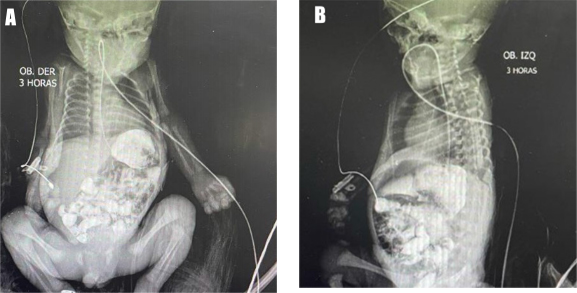

Bajo alta sospecha de presentar una obstrucción intestinal por cuadro clínico previamente descrito, se indica una serie gastrointestinal superior con medio de contraste que reporta dilatación gástrica y dilatación de la primera y segunda porción del duodeno, así como escaso paso de medio de contraste al intestino distal. Este hallazgo corresponde a estenosis duodenal (Figura 2).

Figura 2 A. Gran distensión de la cámara gástrica asociado a pasaje filiforme de sustancia de contraste a través de antro pilórico; B. Adecuado tránsito de sustancia de contraste a través de asas delgadas y gruesas. No se observó imágenes de adición ni fístulas

El diagnóstico generalmente se realiza por la presencia de una doble burbuja de aire (en una radiografía simple de abdomen), pero puede confirmarse mediante una serie gastrointestinal superior que demuestre obstrucción duodenal 8. Pero no representa el diagnóstico definitivo debido a que puede verse en otras afecciones, como la atresia duodenal y la malrotación intestinal 15. Los hallazgos en la serie gastrointestinal superior incluyen un estrechamiento duodenal con un estrechamiento excéntrico o concéntrico de la segunda porción del duodeno, y dilatación simétrica del duodeno proximal 4. Sin embargo, no se requieren pruebas adicionales debido a que la sospecha de obstrucción duodenal completa o parcial requieren intervención quirúrgica 15. Por lo tanto, se realiza un diagnóstico definitivo en la laparotomía 8. En el caso de nuestro paciente fue necesario complementar el estudio con la serie gastrointestinal superior con contraste, en la que se evidenció la dilatación de la porción superior y descendente del duodeno, junto a la estenosis duodenal distal. Este fue el motivo por el cual se ingresó a laparotomía exploratoria en su décimo primer día de vida.

El caso presentado comenzó a dar manifestaciones de distensión abdominal y vómitos en el primer día de vida, tal y como se describen los casos en etapa neonatal en la literatura. Se corroboró el diagnóstico con el examen radiográfico de pie, con la imagen típica de "doble burbuja" 15, sumado a la estrechez duodenal evidenciada mediante la serie gastrointestinal superior con contraste. Lo anterior concuerda con la literatura respecto a la limitación diagnóstica que tiene el páncreas anular 14; sin embargo, el diagnóstico definitivo y terapéutico es la intervención quirúrgica 13. Durante el acto quirúrgico se identificó que la obstrucción intestinal era ocasionada por una estenosis duodenal secundaria a páncreas anular, por lo cual se procedió a realizar la técnica quirúrgica de elección (cirugía de Kimura) sin presentar complicaciones inmediatas.